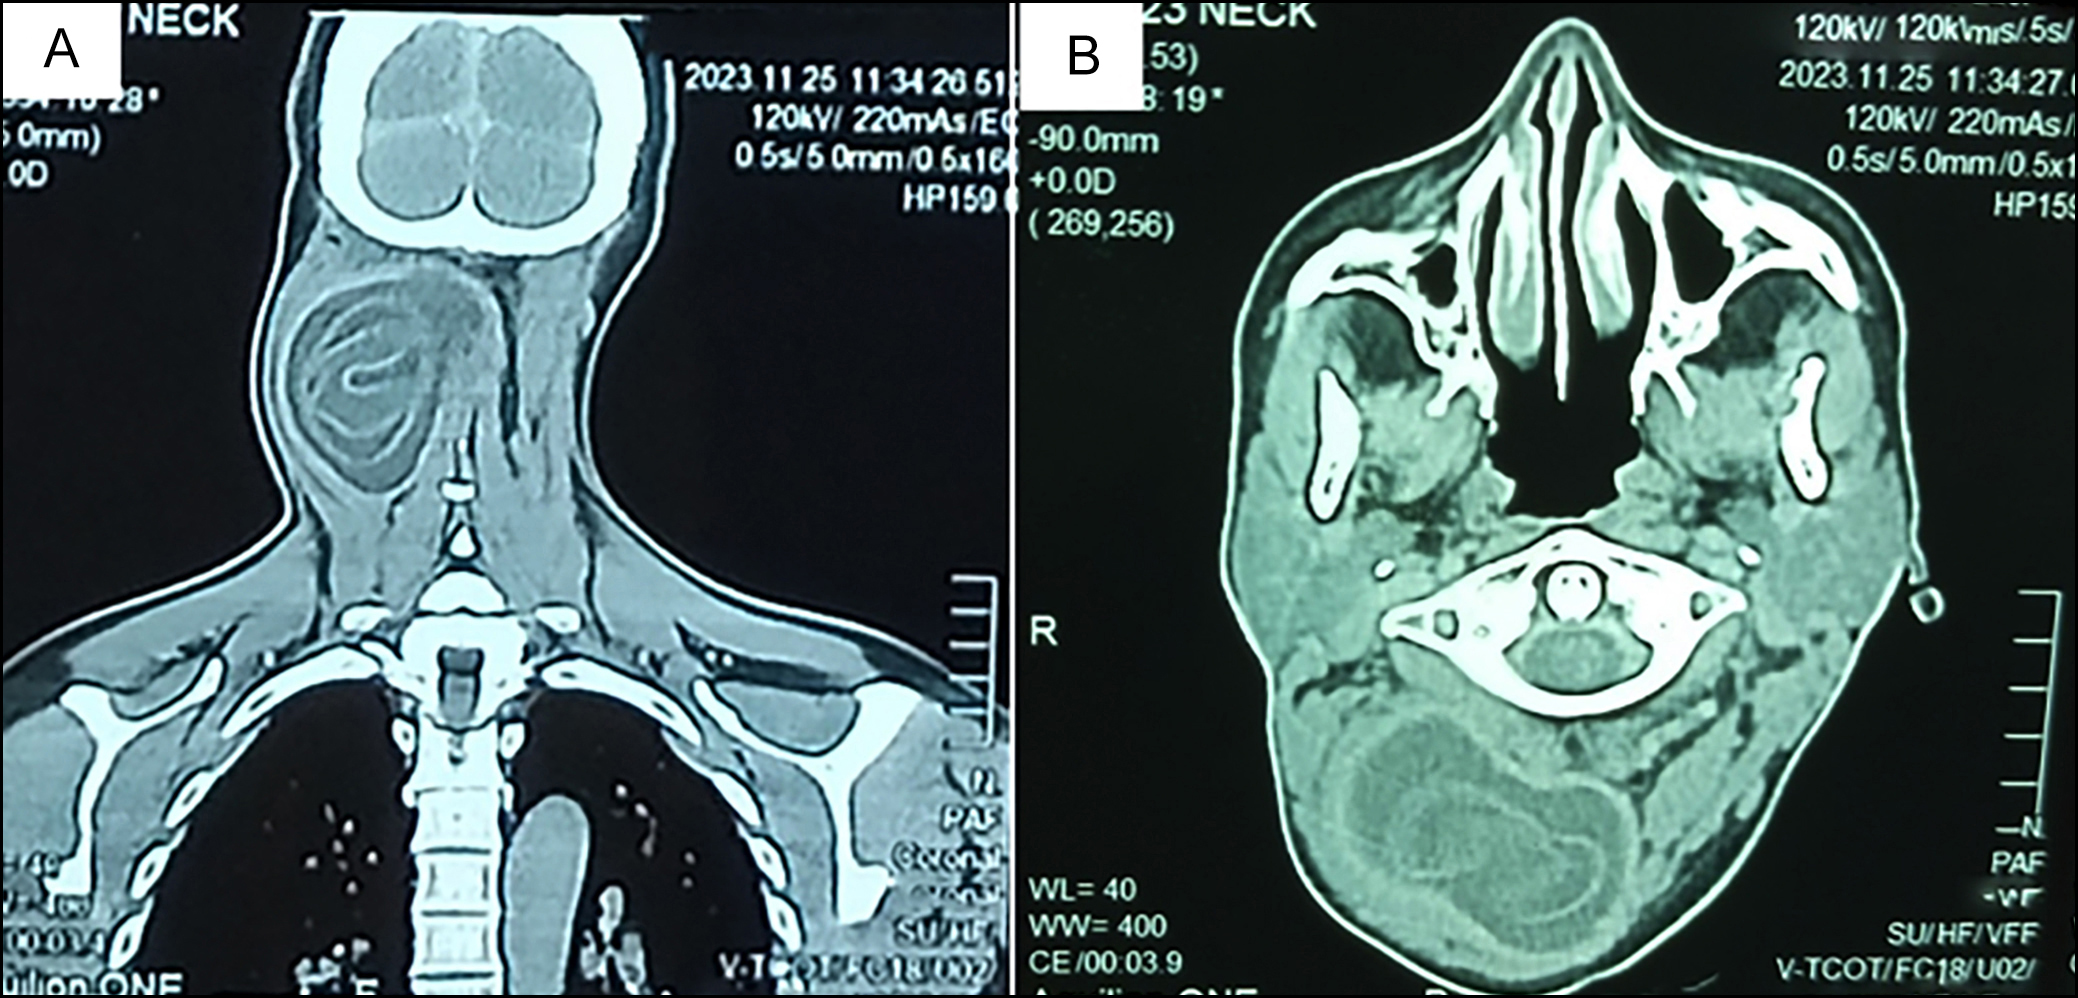

Magnetic resonance imaging (MRI) of the neck revealed a well-defined, round-to-oval cystic lesion with abnormal signal intensity, and an internal detached floating membrane within the soft tissues of the right neck region. The lesion extended into the right paraspinal area from the C1 to C4 vertebral levels. It demons- trated iso-intense signal on T1-weighted imaging (T1WI) and hyperintense signal on T2-weighted imaging (T2WI), with patchy areas of restricted diffusion on diffusion-weighted imaging (DWI) and corresponding low signal intensity on apparent diffusion coefficient (ADC) mapping. Post-contrast sequences showed peripheral enhancements without surrounding oedema. The lesion measured approximately 4.4 × 7.2 cm (anteroposterior × transverse) on axial T2WI and 6.9 cm craniocaudally on coronal T2WI. Posterolaterally, it displaced the splenius capitis, semispinalis capitis, longissimus capitis, and trapezius muscles on the right side; anteromedially, it compressed and displaced the right oblique capitis inferiorly; and medially, it displaced the ligamentum nuchae towards the left (Figure 2 and 3). The diagnosis was confirmed by  a  positive  Echinococcus  antibody  titre.

Figure 2: T2-weighted sagittal (A, B) and axial (C, D) MRI images of the neck demonstrating a well-defined, hyperintense, round-to-oval cystic lesion with an internal detached floating membrane within the soft tissues of the right side of the neck.